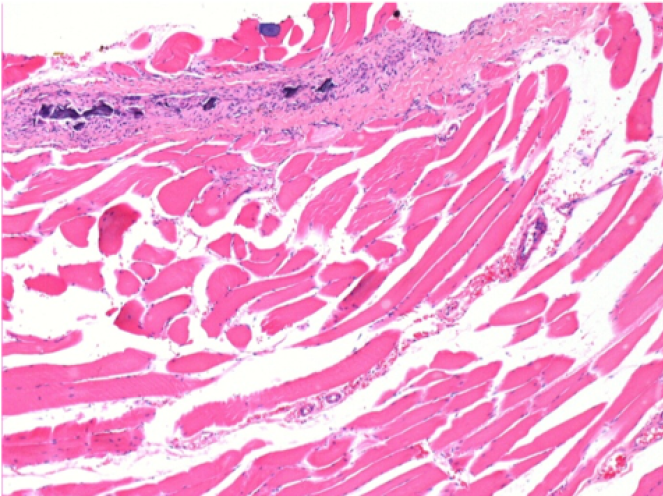

09

7 mesi dopo Iniezione di Endopeel

Scatola Nr 5

7 mesi (Giorno210) dopo iniezione IM di 0.1ml di Endopeel nel muscolo pretibiale destro ( Dx).

Restitutio ad integrum completo dopo 7 mesi

Sx : Controllo-100x-Giorno210

Dx:100x-Giorno210

Sx :Controllo 50x-Giorno210

Dx:50X-Giorno210